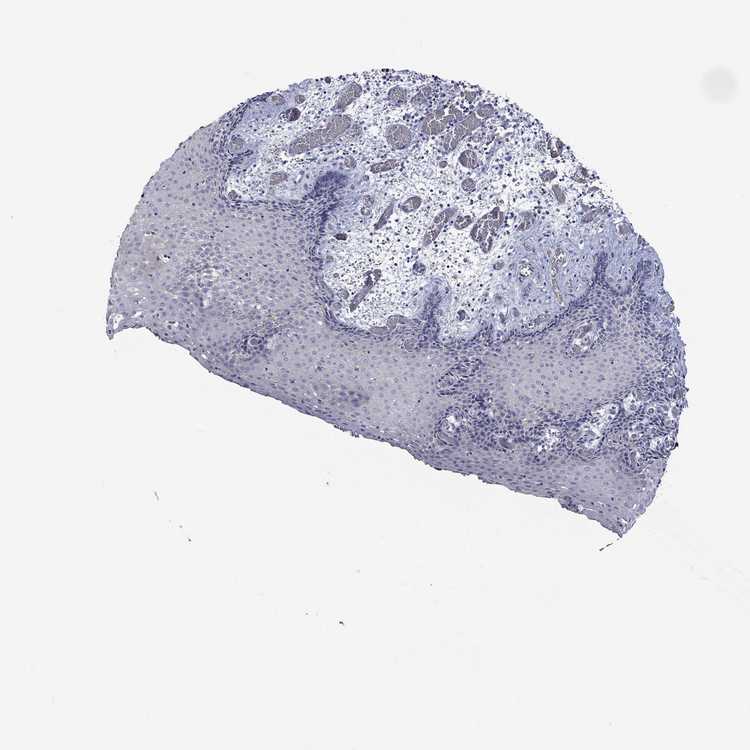

ESOPHAGUS - Antibody stainingi

Antibody staining in the annotated cell types in the current human tissue is reported as not detected, low, medium, or high, based on conventional immunohistochemistry profiling in selected tissues. This score is based on the combination of the staining intensity and fraction of stained cells.

Each image is clickable and will lead to virtual microscopy that enables deeper exploration of all samples and also displays staining intensity scores, fraction scores and subcellular localization as well as patient and tissue information for each sample.

Antibody HPA006135Antibody HPA071007

Squamous epithelial cells Not detectedNot detected